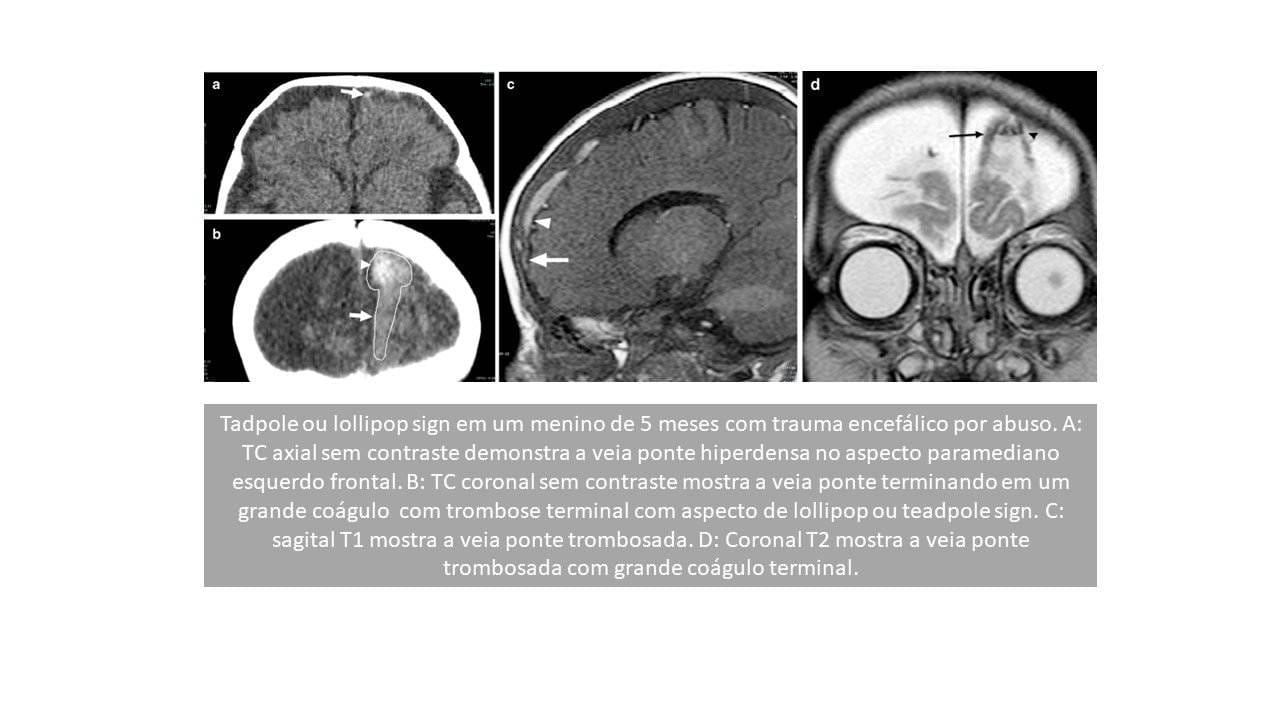

Tadpole sign (Sinal do girino)

Estudos anteriores compararam a aparência na TC e RM da trombose da veia ponte com a de um girino. Esse achado foi prevalente em > 70% dos casos. O corpo do girino é representado pelo material trombótico de formato oval a redondo dentro do espaço subaracnóideo; a cauda é representada pela veia em ponte rota e expandida pelo sangue coagulado. No entanto, em uma revisão subsequente, apenas 36% dos casos com sinal de girino, conforme observado no SWI axial, representaram trombose da veia em ponte (FIGURA 1).

Lollipop sign (Sinal do pirulito)

O lollipop sign na RM (particularmente no GRE), onde a veia ponte parassagital termina abruptamente em um coágulo de sangue, sem evidências de drenagem para o seio venoso. A cabeça do pirulito é o coágulo de sangue no espaço subaracnóide e o bastão é a veia ponte com trombose terminal. Essas veias ponte terminam abruptamente e não drenam para o seio sagital superior.